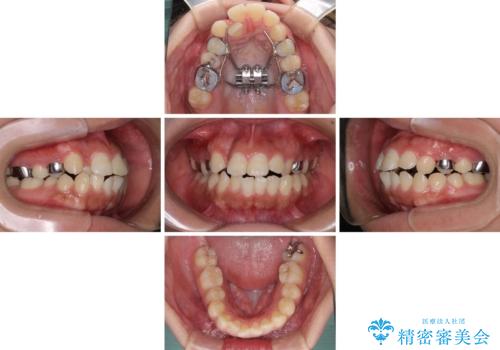

上顎歯列の横幅が狭く、下顎大臼歯の歯軸が舌側に倒れていたため、急速拡大装置により上顎骨を側方に拡大し、咬み合わせを改善することとしました。

上顎歯列幅を拡大したことで、デコボコを容易に解消することができるようになったため、抜歯により得られたスペースを口元の突出感改善に利用することができました。